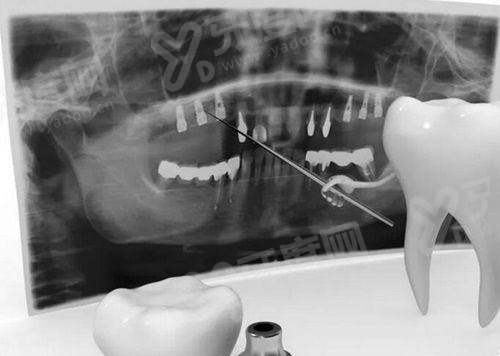

1、邵阳雅贝康口腔医院医院引进了数字化口腔CBCT设备,能够清晰地显示牙齿、牙槽骨等口腔内部结构,为种植牙、牙齿矫正等治疗提供精细的影像支持,提高治疗的正确性和成功几率。